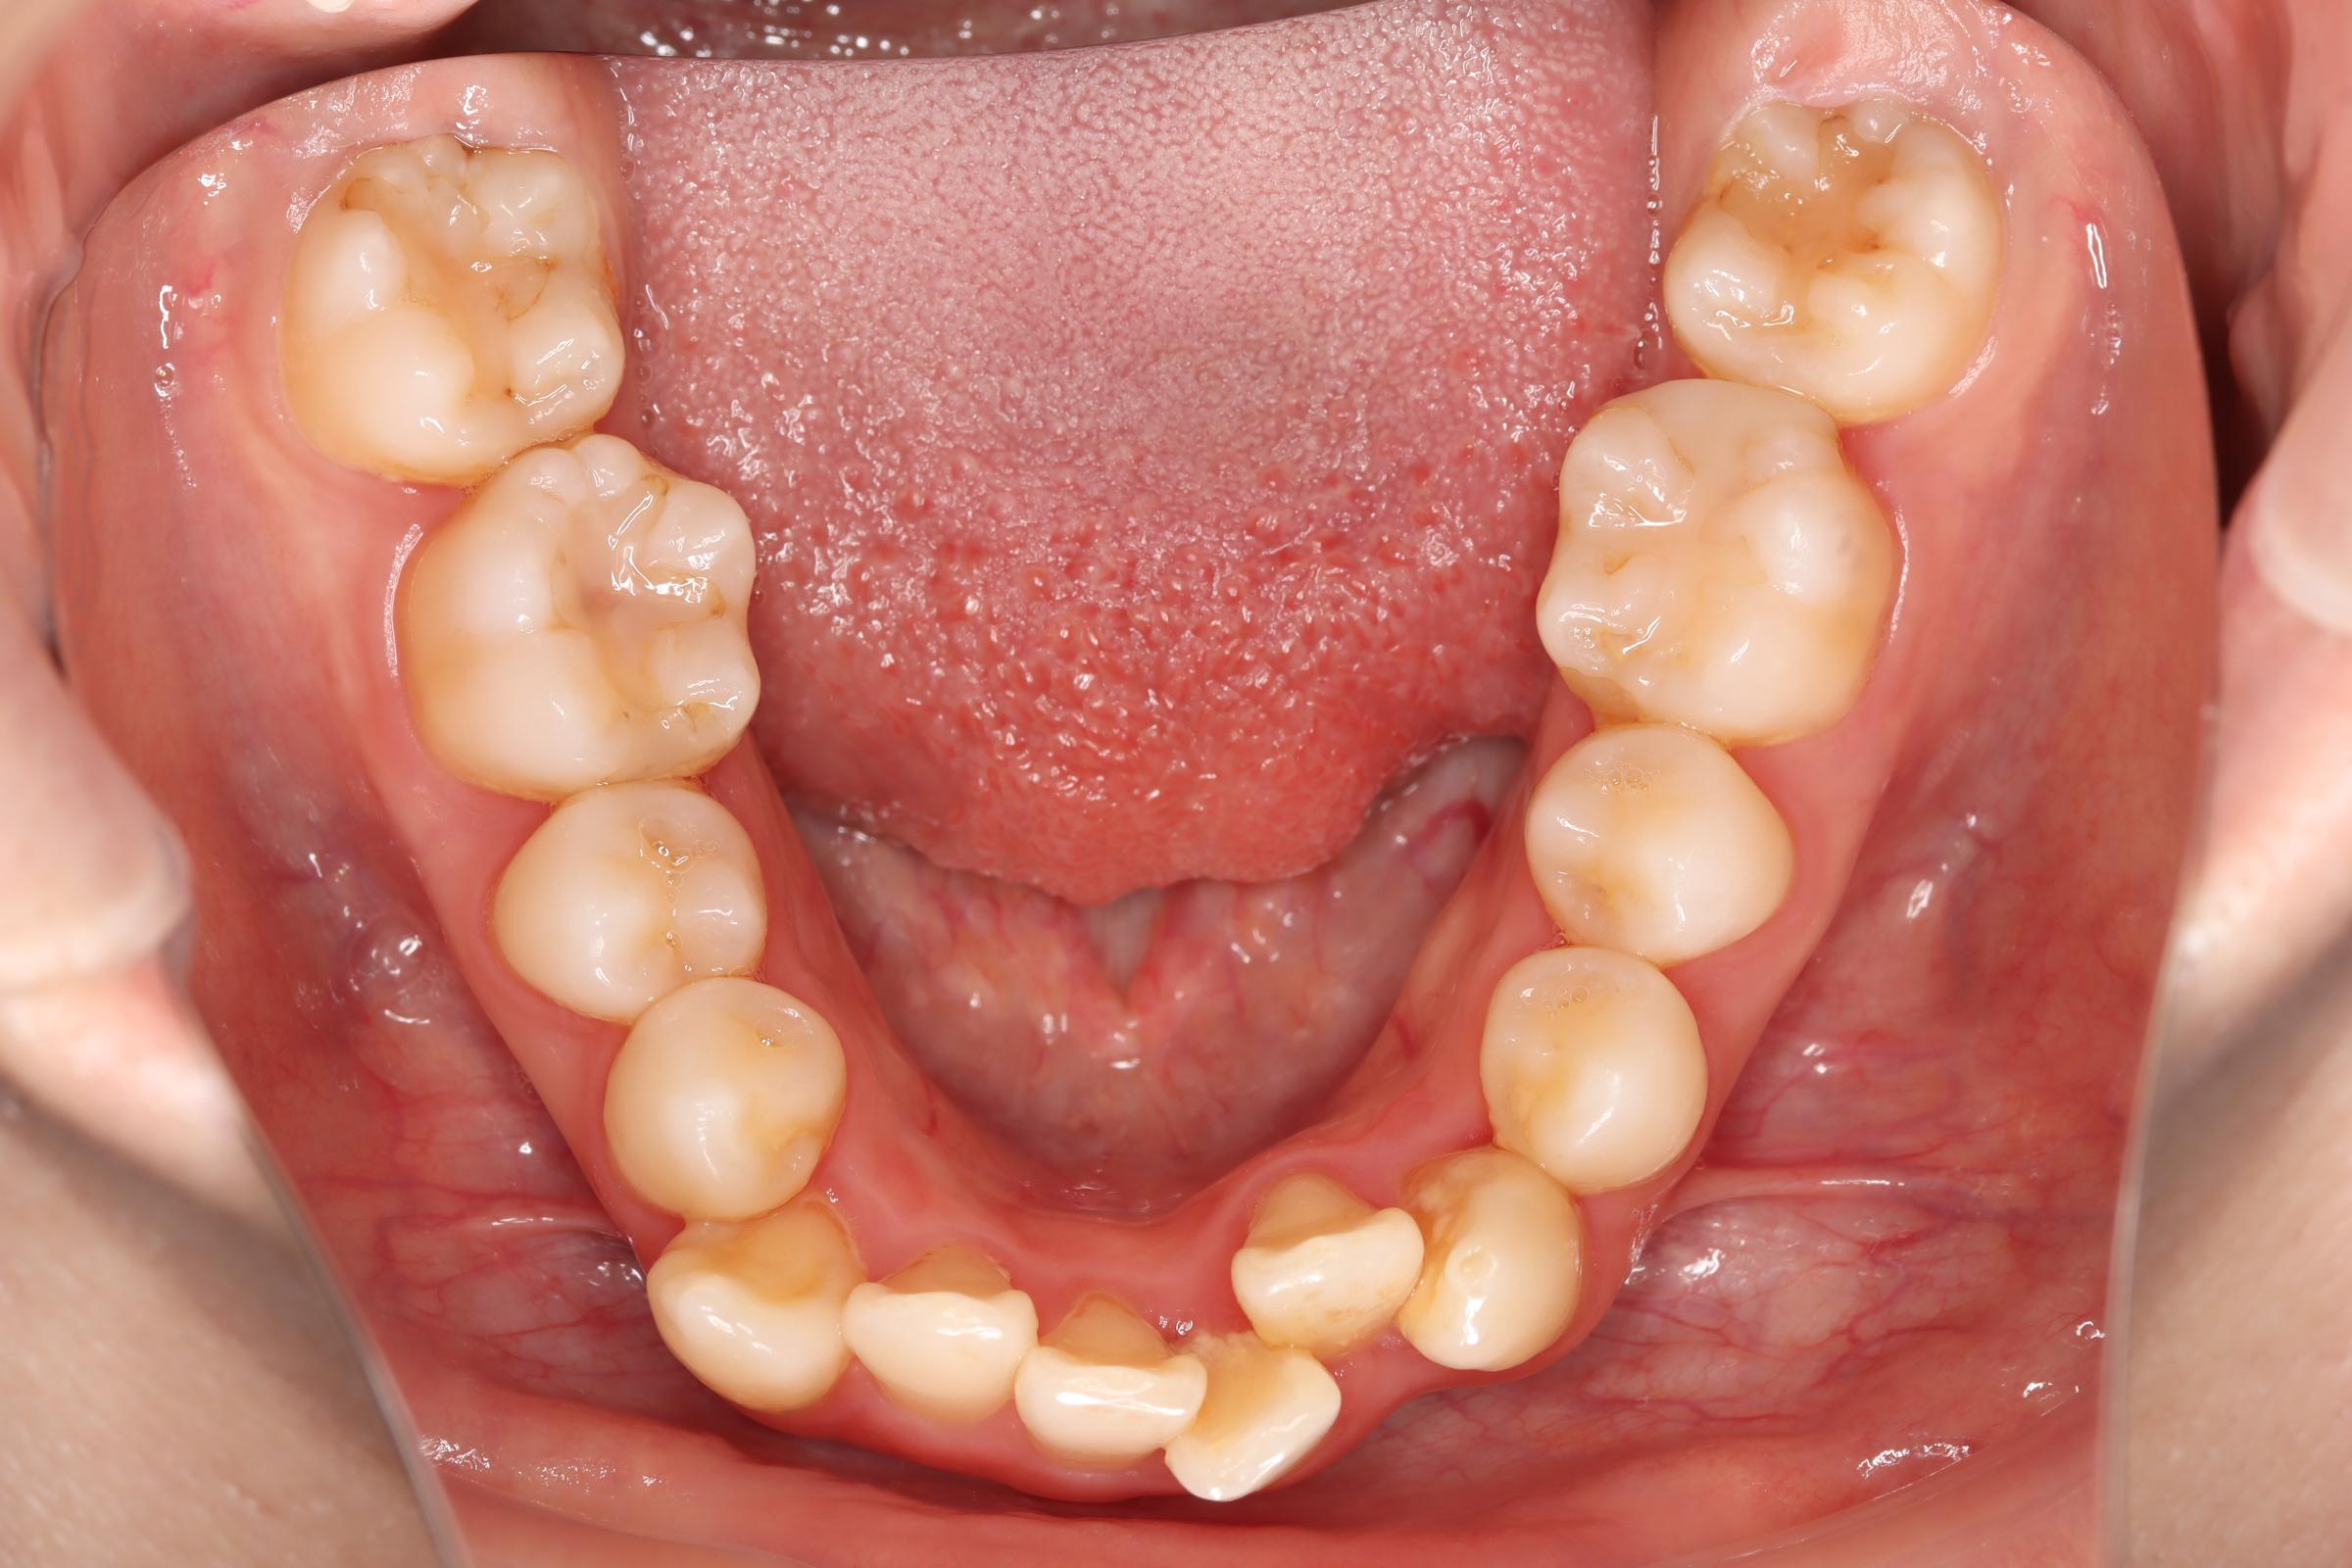

舌側(リンガル)矯正での叢生(ガチャ歯)の治療

口腔内の変化

| 治療前 | SNSなどで「ガチャ歯」と呼ばれている、見た目のがたつきを治したかった患者さんです。 骨格的な問題はありませんでしたが、上下の前歯が唇側傾斜しており、上下顎前突症で口元の突出感がありました。 |